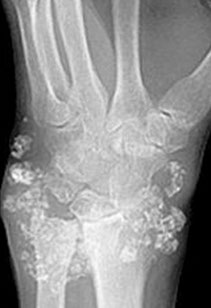

Imaging: erosion of tufts of terminal phalanges and subperiosteal cortical resorption, esp on the radial side of the middle phalanges

Micro: Osteoclasts line cystic spaces (tunneling), which also have a very fibrous stroma, inc formation of woven bone, and peritrabecular fibrosis, MNGCs

Labs: Inc Ca and ALP, low PO4

- hyperparathyroidism: dec Ca, inc PO4 if renal etiology and normal PO4 if extrarenal etiology

Osteitis fibrosa cystica